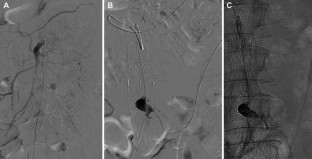

Fig. 2